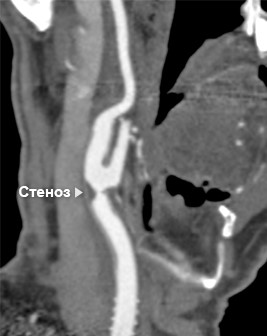

На сегодняшний день это одна из наиболее распространенных методики оценки состояния внутренних органов посредством лучевой диагностики. Процедура заключается во введении контрастного вещества в локтевую вену через автоматический шприц. Благодаря МСКТ-ангиографии всего за 5-10 мин. доктор сможет с высочайшей точностью определить наличие тех или иных заболеваний сосудистой системы – артериального расширения (аневризмы), стеноза (сужения), окклюзии (полной закупорки). Кроме того, обнаружит сосудистую опухоль, аномалию строения сосуда и так далее.

Минимальное количество времени, требуемого для проведения диагностики, существенно снижает лучевую нагрузку на больного. МСКТ-ангиография является информативной и точной методикой, позволяющей получить трехмерное изображение тканей и органов с высокой степенью разрешения.

Единственным недостатком метода является статичность, т.е. невозможно получить изображение в режиме реального времени. При этом нельзя увидеть процесс кровенаполнения сосуда и оценить, в каком направлении движется кровь

Сонные артерии на компьютерном томографе в режиме 3D-реконструкции

Здоровая сонная артерия на МСКТ

Пораженная сонная артерия на МСКТ